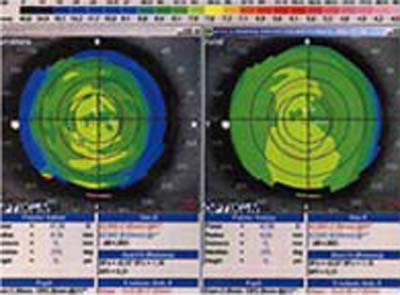

2 - Topografía de alto poder

3 - Topografía de bajo poder

Con esta metodología, los poderes altos de la superficie corneal son representados en colores cálidos como el amarillo, naranja y rojo (Foto 2) mientras que las áreas de bajo poder se las representa en colores más frios como el verde y el azul. ( Foto 3), facilitandose así visualización de los efectos de la cirugía refractiva y la comprensión de sus resultados ( Foto 4 y 5)